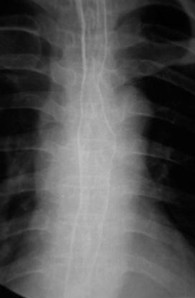

女,51歲,以“進(jìn)行性吞咽困難1年”為主訴于2007年2月19日入院。鋇餐造影、胃鏡示食管上段占位性病變,確診為食道鱗癌(圖1),拒絕手術(shù),行放療+今又生治療。食道鏡下瘤內(nèi)注射今又生,1×1012VP/次/周×6,放療在今又生注射3 d后開始,采用常規(guī)分割三野等中心照射,劑量65cGY。治療結(jié)束后4周,食管X線、胸部CT顯示腫瘤完全消退(圖4-5)。

放療65GY +今又生6支后